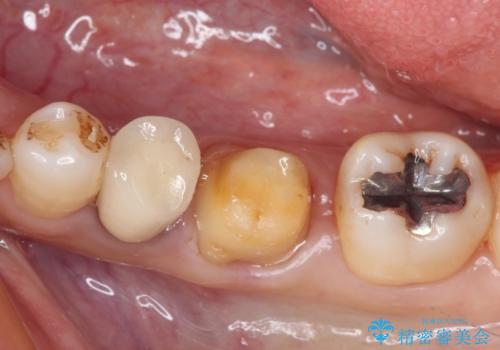

- 奥歯の銀歯をセラミックの白い歯にして、しみる症状も改善したいとのことで来院された患者様です。

知覚過敏の症状が強い歯と、銀歯の範囲や銀歯の下のむし歯が大きい歯は、インレー修復では対応が難しいためオールセラミッククラウンで、インレー修復で対応が可能な歯ではセラミックインレーにて修復することとしました。